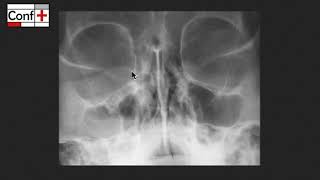

ORL - Ophtalmo 1 - Imagerie CONF +

ConfPlusTV